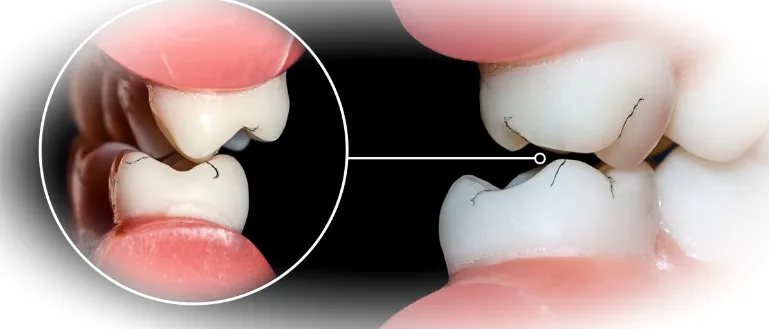

Симптомы могут проявляться по-разному. Некоторые пациенты жалуются на постоянную боль в области челюстей, головные боли по утрам, повышенную чувствительность эмали. Другие замечают, что их зубы стали стираться, могут появляться сколы и трещины на эмали. Также распространены проблемы со сном, храп и даже повреждения протезов.

Если вовремя не обратить внимание на эти тревожные сигналы, бруксизм может привести к серьезным осложнениям, таким как повреждение височно-нижнечелюстного сустава, нарушение прикуса, а в некоторых случаях и к потере зубов.